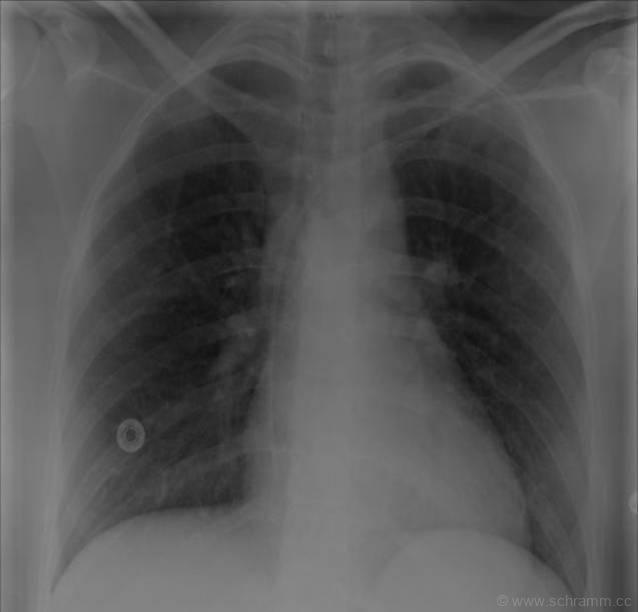

In diesem Thoraxröntgen zeigt sich ein zentraler Venenkatheter, welcher über die